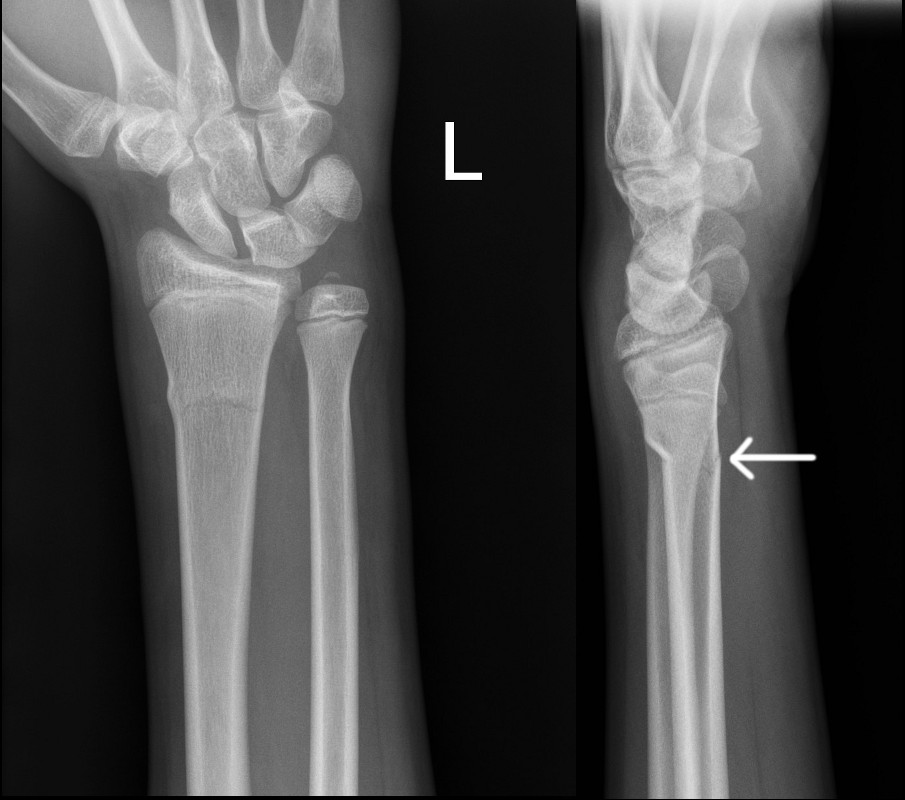

Buckle fractures that should not be managed in a wrist splint

Left image: Buckle fracture with volar angulation (see arrow)

Right image: Disruption of cortex of volar aspect of radius (see arrow)